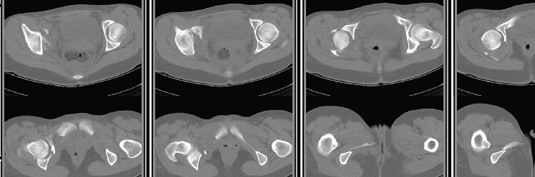

30/11/04 |  30/11/04 |  30/11/04 |  14/12/04 |  14/12/04 |  14/02/05 |  14/02/05 |  21/02/05 | Уважаемые коллеги! Случилось вторичное смещение вертлужной впадины после операции. Посоветуйте, что делать. Пациентка 18 лет. Травма 19.11.04. D.s.: Закрытыый Т-образный высокий перелом правой вертлужной впадины. Закрытый перелом м\мыщелкового возвышения левой б\берцовой кости. 9.12.04 операция - открытая репозиция, остеосинтез переломам вертлужной впадины. 30.12.05 выписаны на амбулаторное лечение с рекомендациями не вставать на правую ногу. 14.02.05 при контрольном осмотре на Р-граммах выявлено вторичное смещение передней колонны. Клинически подвывиха нет, имеется умеренная приводящая контрактура правого тазобедренного сустава, гипотрофия мышц н\конечностей. Госпитализирована в травмотделение. Выполнено КТ. Имеется смещение передней колонны кнутриЮ диастаз 8 мм. Посоветуйте пожалуйста, что предпринять в данной ситуации.

У больной имеется диастаз лонных и седалищных костей, то есть "разорвано" тазовое кольцо. В перспективе возможно образование ложного сустава на уровне основания лонной кости с болевым синдромом, поскольку седалищная кость не срастется.

2. ограничить двигательную активность до 6 мес. (не нагружать ногу, носить тазовый корсет-пояс и т.д.) с контролем сращения. Вроде бы на Р-граммах угадывается слабая тень формирующегося костного мостика по l. iliopectinea, это место в представленные срезы КТ не попало. Если к 6 мес. ничего не нарастет, то см. пункт 1.